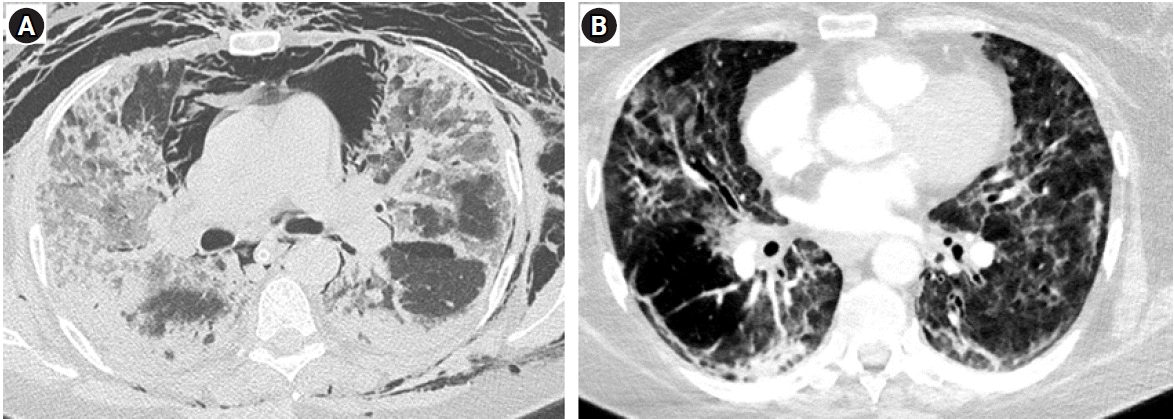

A 56-year-old female presented to the intensive care unit with shortness of breath, non-productive dry cough and worsening hypoxemia (SpO2 at admission of 70% on room air). Her medical history included hypertension, obesity (body mass index, 40.2 kg/m2) and stable bronchial asthma. Severe acute respiratory syndrome coronavirus 2 (SARS-CoV-2) COVID-19 test was positive via polymerase chain reaction test. Improvement of oxygenation was attempted initially by total face continuous positive airway pressure ventilation mask with 0.5 FiO2 (Total Face DiMax; Dimar Medical Devices, Medolla, Italy) but did not yield improvement. She was intubated and mechanical ventilation was initiated using Bilevel mode (Puritan Bennett 840; Medtronic, Minneapolis, MN, USA) that also proved ineffective (PEEP high [PEEPh], 28; PEEP low [PEEPlow], 14 cm H2O; inspiratory: to expiratory ratio, 1:1; PEEP plat [Pplat], 30 cm H2O; Vt, 420 ml; FiO2, 0.8) despite using prone positioning. Two days later, her condition worsened by reaching PaO2 to FiO2 ratio of 75 according to Berlin ARDS criteria (PaO2, 60 mm Hg; FiO2, 0,8; PEEP, 10 cm H2O; Pplat, 35 cm H2O) (Figure 2A). Calculated Murray score for acute lung injury was 3.3 with a corresponding predicted mortality of 45%. Therefore, ECMO center was consulted and patient transferred.

During the next three days, she was on mechanical ventilation and unable to wean due in part to bacterial superinfection (Klebsiella pneumoniae) that necessitated frequent bronchoscopies. Pressure supported ventilation (PSV) mode with 3LV PMLV was used: RR 24/min, PEEP 8 cm H2O, PEEPh 6 cm H2O, with PEEPh being used in 50% of all respiratory cycles. PSV was used on top of all PEEP levels with peak inspiratory pressure rarely exceeding 30 cm H2O. She was extubated on day 14 (Figure 2B), with neurologic status slowly returning to normal. At discharge she was neurologically intact, walking spontaneously with basic walking assistance device. She was transferred to an intensive rehabilitation facility of her own choosing a month after admission.